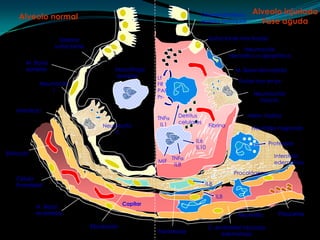

Alveolo injuriadoFase agudaAlveolo normal Desprendimiento epitelio bronquialSurfactante inactivadoSistemasurfactanteNeumocitoINecrótico o apoptóticoM. Basal epitelialMacrófago alveolarM. Basal denudadaLtFRPAFPr-Fluído rico en pr-NeumocitoINeumocitoIIintactoIntersticio DetrituscelularesMem. hialinaTNFIL1Fibrina NeumocitoIINeutrófilo migrandoIL6IL10Proteasas Eritrocito Intersticio edematosoTNFIL8MIFProcolágeno CélulaEndotelial IL8IL8Capilar M. Basal endotelialPlaquetas Neutrófilo Fibroblasto C. endotelial injuriadaedematosaFibroblasto

Alveolo injuriadoFase agudaAlveolonormal Desprendimiento epitelio bronquialSurfactante inactivadoSistemasurfactanteNeumocitoINecrótico o apoptóticoM. Basal epitelialMacrófago alveolarM. Basal denudadaLtFRPAFPr-Fluído rico en pr-NeumocitoINeumocitoIIintactoIntersticio DetrituscelularesMem. hialinaTNFIL1Fibrina NeumocitoIINeutrófilo migrandoIL6IL10Proteasas Eritrocito Intersticio edematosoTNFIL8MIFProcolágeno CélulaEndotelial IL8IL8Capilar M. Basal endotelialPlaquetas Neutrófilo Fibroblasto C. endotelial injuriadaedematosaFibroblasto